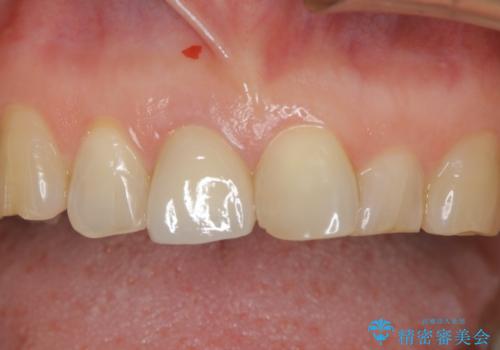

- 左上奥歯の銀歯のやり変えを希望された患者様です。

白くしたいとの事だったので形態・切削量を考慮し、セラミックインレーでの治療を計画しました。